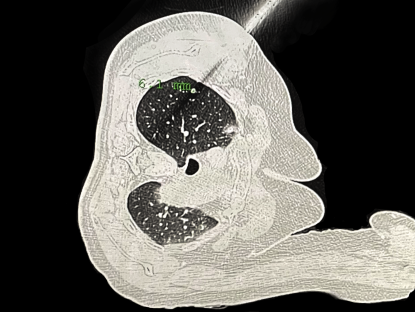

患者准备接受机器人导航穿刺手术。本文图片均为上海市东方医院供图

经皮穿刺肺活检术是一项在CT引导下开展的、进一步查验病理“真身”的方法,而基因检测与PD-L1表达检测是靶向治疗与免疫治疗的关键参考指标,这些检查对帮助临床医生为吴女士制定后续的个体化精准治疗方案,起到至关重要的作用,因此活检势在必行。

“在穿刺活检过程中,肺小结节容易因呼吸运动而发生移动,不但增加了穿刺取样的难度,也可能导致假阴性结果的出现,而且传统方法需要多次CT扫描来调整针位,以实现准确穿刺结节的目的,这也会引起气胸、咯血等并发症的发生,尤其是遇到病灶微小、位置隐匿的情况,难度更是升级。”周彩存说。

穿刺定位针到位。

团队方面介绍,本次研发的穿刺手术导航机器人采用“CT影像和智能传感一体化技术”,一次扫描,系统就可完成患者坐标与定位系统坐标系的配准,再根据手术路径规划,即可实现穿刺器械的准确导航定位。该项目的临床研究也是周彩存教授团队首个医疗器械类项目。

团队进一步透露,由于机器定位达亚毫米级,这从根本上提高了经皮肺穿刺活检的精准度,在该系统的辅助下,穿刺效率明显提高,气胸和出血风险显著降低;整个操作流程省去了手术过程中粘贴标识、测绘穿刺点及“分步进针”等步骤,原本30分钟左右的传统穿刺手术,能够有效缩短手术时间至8-10分钟。此外,机器人的使用并不改变医生传统穿刺习惯,无需特殊的光学、电磁类配件的安装与配准,经过培训的医生可快速、精准使用机器。同时,最让患者担心的有关CT扫描次数和受辐射剂量也大大降低。